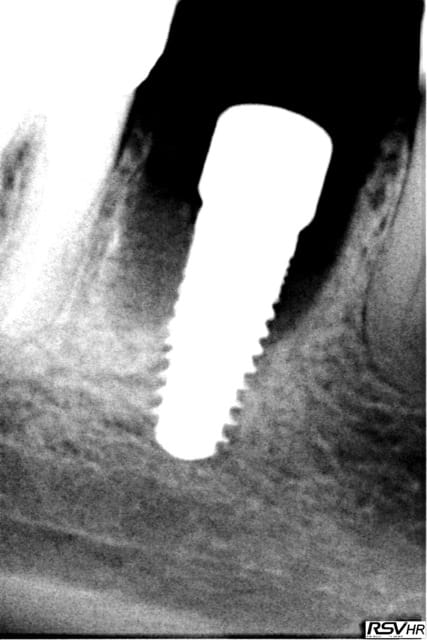

même si je me redirige plutôt vers Zimmer avec une insertion primaire supérieur (à mon avis ) voici un cas de plusieurs années

j'avais gardé une racine distale de 46 (montage 2 ccm soudées au début 4647- avec diastème avec 45 ;2008;le montage

n'a pas tenu longtemps=extraction racine distale et

implantation immédiate legacy2 7 mm(2011)

et ccm transvissée 3 mois après

radio à 2015